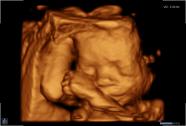

3D/4D-Ultraschall für Schwangere

Seit März 2019 steht ein neues 3D/4D-Ultraschallgerät für faszinierende Eindrücke von Ihrem Baby zur Verfügung.